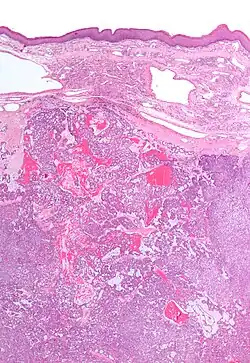

| Low magnification micrograph of a polymorphous low-grade adenocarcinoma, showing the typical variation of architectural arrangement. H&E stain. | |

PLGAs consist of a monomorphous cell population that has a varied histologic morphology.

Microscopically, its histology can be confused with an adenoid cystic carcinoma and a pleomorphic adenoma.